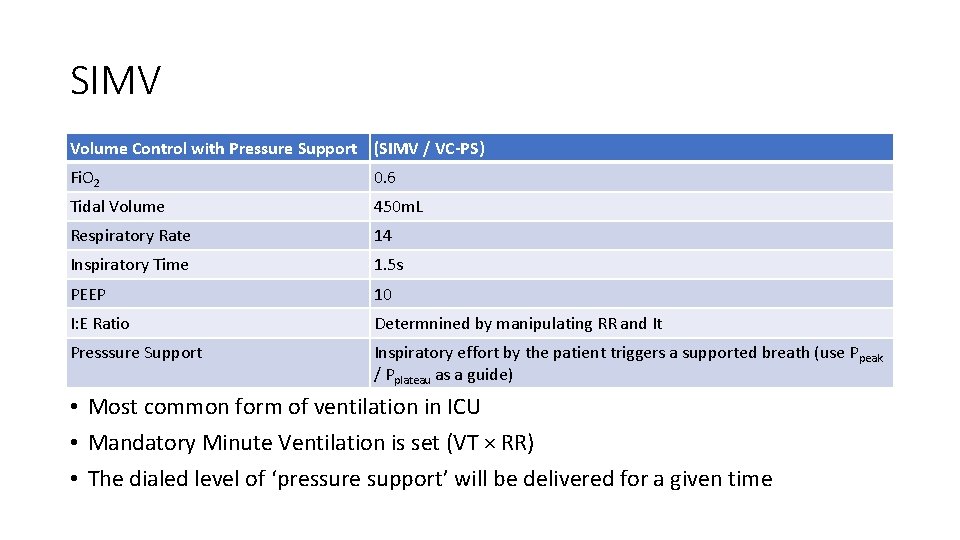

SIMV Volume Control with Pressure Support (SIMV / VC-PS) Fi. O 2 0. 6 Tidal Volume 450 m. L Respiratory Rate 14 Inspiratory Time 1. 5 s PEEP 10 I: E Ratio Determnined by manipulating RR and It Presssure Support Inspiratory effort by the patient triggers a supported breath (use Ppeak / Pplateau as a guide) • Most common form of ventilation in ICU • Mandatory Minute Ventilation is set (VT × RR) • The dialed level of ‘pressure support’ will be delivered for a given time